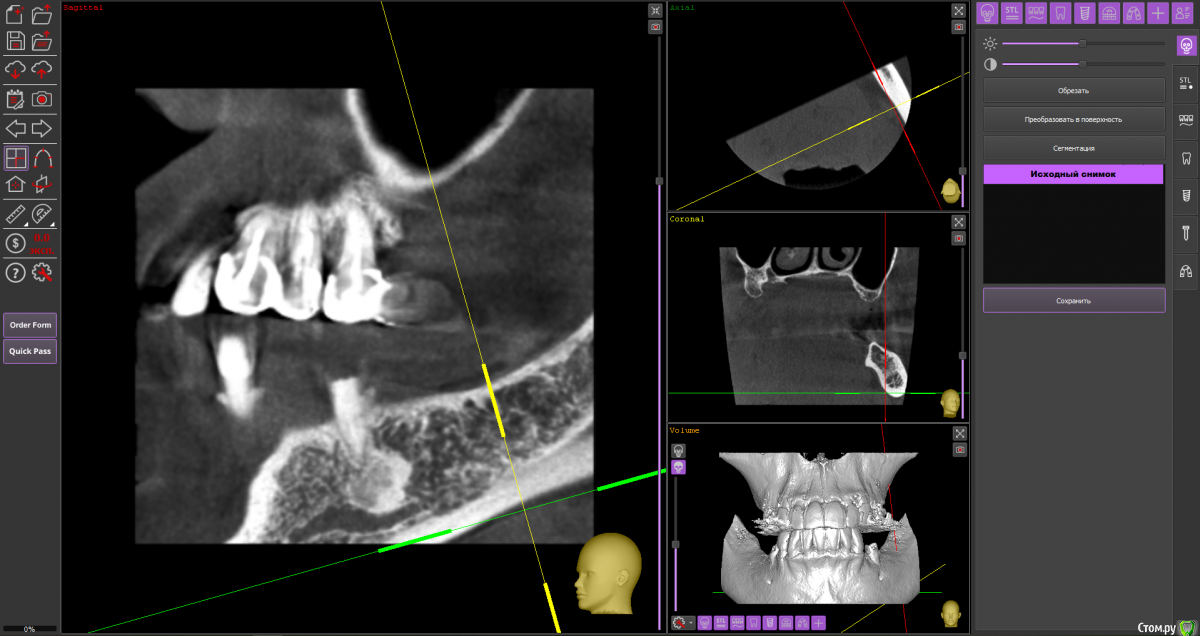

almaz7888 Опубликовано 11 февраля, 2021 Поделиться Опубликовано 11 февраля, 2021 (изменено) Доброе утро коллеги! Подниму тему. Данной пациентке планируется имплантация для замещения концевых дефектов на нижней челюсти. Зуб 3.5 думал удалить во время операции. Образование в области 3.5 это просто склероз кости? В области ментального отверстия справа также имеется какой-то очаг но меньших размеров. Изменено 11 февраля, 2021 пользователем almaz7888 Ссылка на комментарий